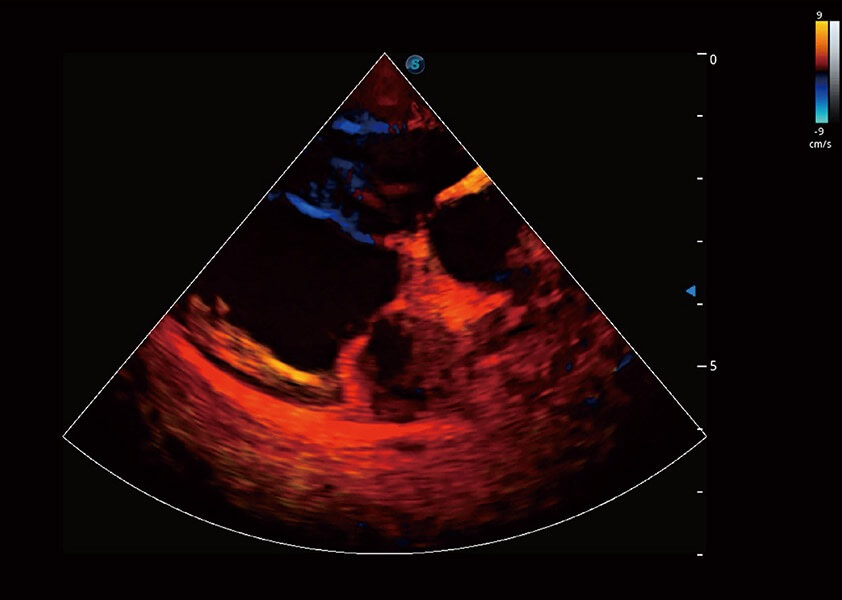

ProPet 60 作为一款高端台式动物超声设备,为动物医生的日常诊断提供了一系列贴合动物临床需求、解决临床实际问题的高级成像功能。凭借全系列高清探头,满足医生对腹部、心脏、生殖、浅表、肌骨等成像的所有需求,切实帮助您提升检查效率,提高诊断信心。

兽用彩色多普勒超声诊断系统

动物是人类最亲密的朋友和最值得信赖的伙伴。竞技宝(JJB)官方网站也一直致力于探索动物专用的超声影像解决方案。 全新推出的ProPet系列,是竞技宝(JJB)官方网站在动物超声影像智能化、专业化、精准化的一次跨越式革新。动物不能用言语来表述自己的不适,通过超声影像,ProPet系列搭建了动物医生与不同物种沟通的“桥梁”,为动物医生注入了“治愈之力”。